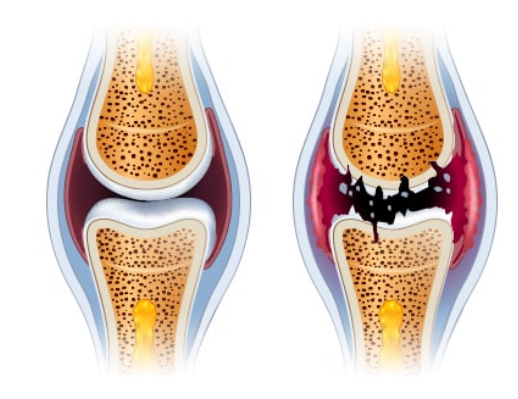

연골의 필수 성분인 글루코사민은 우리 몸에서 원래 스스로 생성되는 성분입니다. 그러나 나이가 들어 가면서 글루코사민 생성 능력은 현저히 감소하게 됩니다. 이에 따라 자연스럽게 관절연골의 완충 능력은 나빠지게 되고, 손상받기 쉬운 상태가 되어 버립니다. 그리고 이 손상이 염증을 유발합니다. 이것이 바로 관절염입니다.

줄어든 글루코사민 생성능력만큼 음식이나 영양제를 통해 글루코사민을 충분히 공급해주면면 연골의 파괴를 막을 수 있고, 연골 세포의 증식을 촉진시킬 수 있습니다. 그러므로, 적절한 글로코사민 섭취는 관절염 등 관절 질환을 앓고 있는 사람들에게 큰 도움을 줄 수 있습니다.